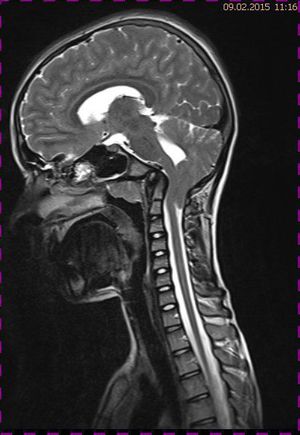

Abb. 1.2 Sagittales MRT (T2 TSE, 1 T): Streckfehlhaltung der HWS und oberen BWS, kein Frakturhinweis oder posttraumatische Myelopathie; die Kleinhirntonsillen reichen bis in das Foramen magnum

Abb. 1.3 Sagittales MRT (T2 TIRM): kein Hinweis auf mikrotrabekuläre Frakturen, regelrecht hydrierte Bandscheiben; die Kleinhirntonsillen lassen sich schlechter abgrenzen

Das Fallbeispiel 1 zeigt im Verlauf eine Komplikation bei einer Arnold-Chiari-Malformation Typ 1 bei einem zum Zeitpunkt der Erstdiagnose 12-jährigen Jungen. Dieser hatte im Sportunterricht einen schweren Medizinball geköpft und ein Stauchungs-trauma der Halswirbelsäule erlitten. Nach anfänglich symptomatischer frustraner Therapie wurde er vom behandelnden Orthopäden zur MRT der HWS überwiesen. Es wurde eine Streckfehlhaltung und flachbogig rechtskonvexe Skoliose diagnostiziert, klinisch bestand ein Torticollis. Eine knöcherne oder ligamentäre Verletzung wie auch eine Schädigung des Rückenmarks bzw. eine intraspinale Bandscheibendislokation konnten bildmorphologisch ausgeschlossen werden.

Trotz weiterer Schmerz- und Physiotherapie konnte keine Beschwerdereduktion erreicht werden. 2 Monate später erfolgte eine MRT des Kopfes zum Ausschluss einer posttraumatischen Veränderung.

Bei dieser Untersuchung wurde übersehen, dass die Kleinhirntonsillen in das Foramen magnum disloziert waren und eine Arnold-Chiari-Malformation mit Erweiterung des 4. Ventrikels und des Aquäduktes inklusive Kleinhirntonsillentiefstand vorlag. Bei zwischenzeitlich auswärtig erfolgtem CT der HWS wurde eine Anlagestörung im kraniozervikalen Übergang beschrieben. Eine Kontrolluntersuchung des Kopfes weitere 4 Monate später dokumentierte neben einem medullären Ödem einen progredienten Tonsillentiefstand, der zur neurochirurgischen Behandlung mit operativer Erweiterung des Foramen magnum führte.